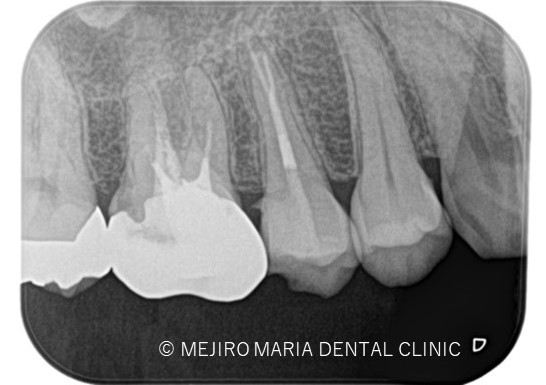

3ヶ月後に経過観察を行い。最終的な根管治療の予後を確認する予定です。 可及的速やかに暫間冠の作製、問題なければ最終補綴処置に移行します。

今回は右上5番に対しての根管治療における、根尖3mmで分岐する根管へのアプローチでした。